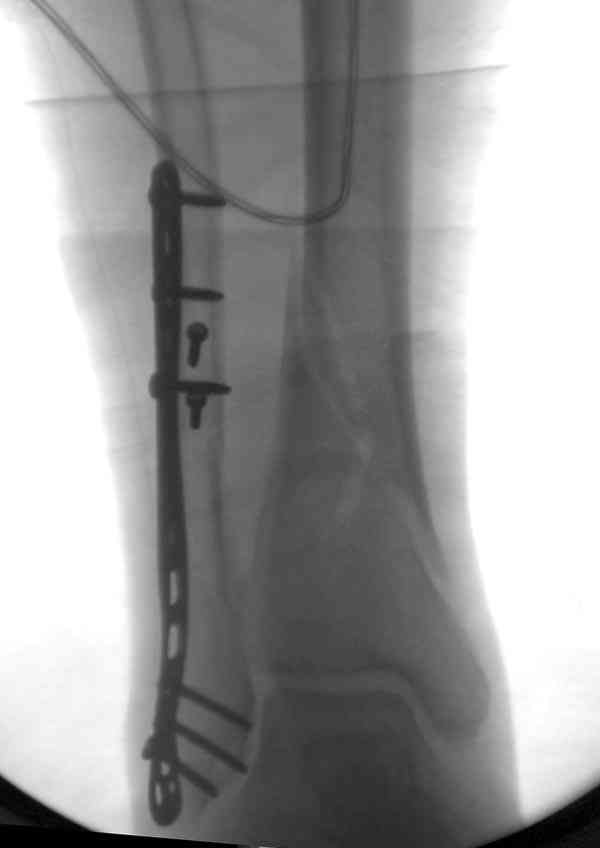

Уже 15 лет в отделении мы активно оперируем свежие переломы ГСС по принципам АО и вполне удовлетворены результатами лечения свежей травмы. В случаях же операций при позднем поступлении или реконструкции после неудачных вмешательств в ряде случаев сохраняется нестабильность ГСС, тенденция к вальгусной деформации. В свежих случаях никогда не приходилось производить шов дельтовидной связки, пластики тоже ни разу не выполнялись. Два примера на снимках.Первый - врач 38 лет, неудачно оперированный в своей больнице с двухлодыжечным переломом, разрывом МБС был повторно оперирован через 8 месяцев. Пытались восстановить длину наружной лодыжки остеотомией, освежили МБС, два месяца функционального лечения без нагрузки на стопу.Сейчас ходит с легкой хромотой, устает к обеду, вальгусное отклонение стопы корригировано супинатором. На Рграммах видны дистрофические изменения латерального эпифиза большеберцовой кости. Первый снимок через 6 месяцев после травмы, операции остеосинтеза болтом-стяжкой, удаленной по причине нестабильности и наличия свища над металлом. Второй снимок через 3 месяца после реконструктивной операции.

Вторая пациентка 34 лет, перелом получала в Испании, где от операции отказалась, дома по приезду сняла скотчкаст и лечилась у костоправов, нагрузка с 3 недели. Операция через 3 мес после травмы. Остеотомия м-б кости, фиксация пластиной, восстановление МБС. Так как медиальная лодыжка подтянулась, суставная щель на ЭОП контроле нормализовалась ограничились латеральным доступом. Реконструкцию заднего края не пытались сделать тк там уже прослеживалась консолидация, а сминать эпиметафиз не хотелось. В настоящее время ходит с тростью \три месяца после операции\, сустав нестабилен-слабость дельтовидной связки. Супинатор и плотные кроссовки дают возможность длительно ходить. Первый снимок сделан в Испании после репозиции, второй через 2 месяца после травмы перед операцией, третий-через 3 мес после операции.